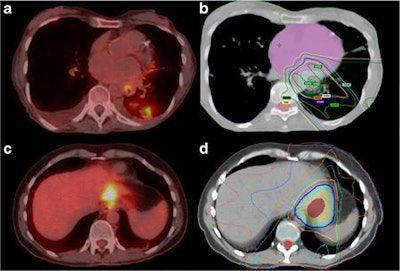

Images show examples of new nonmalignant FDG-avid lesions detected by FDG-PET/CT restaging. A 78-year-old woman (a) with squamous cell carcinoma of the esophagus treated with chemoradiation. PET/CT shows new opacities within the left lower lobe with corresponding areas of FDG activity. The new lesion was within the presumed radiation field (b) and the appearance was most compatible with radiation-induced pneumonitis. Scan was a true-negative for new metastatic disease. A 42-year-old woman (c) undergoing chemoradiotherapy for adenocarcinoma of the distal esophagus. PET/CT shows linear FDG accumulation within the lateral aspect of the left hepatic lobe. A new lesion was within the presumed radiation field (d) and thought to be related to radiation therapy changes. It was a false-positive on MRI, which was required to exclude metastatic disease. Images courtesy of EJNMMI."Currently, there is disagreement between guidelines as to whether all patients should be restaged after chemoradiotherapy," the authors wrote. "At present, little is known about which patients are at risk of developing interval metastases."